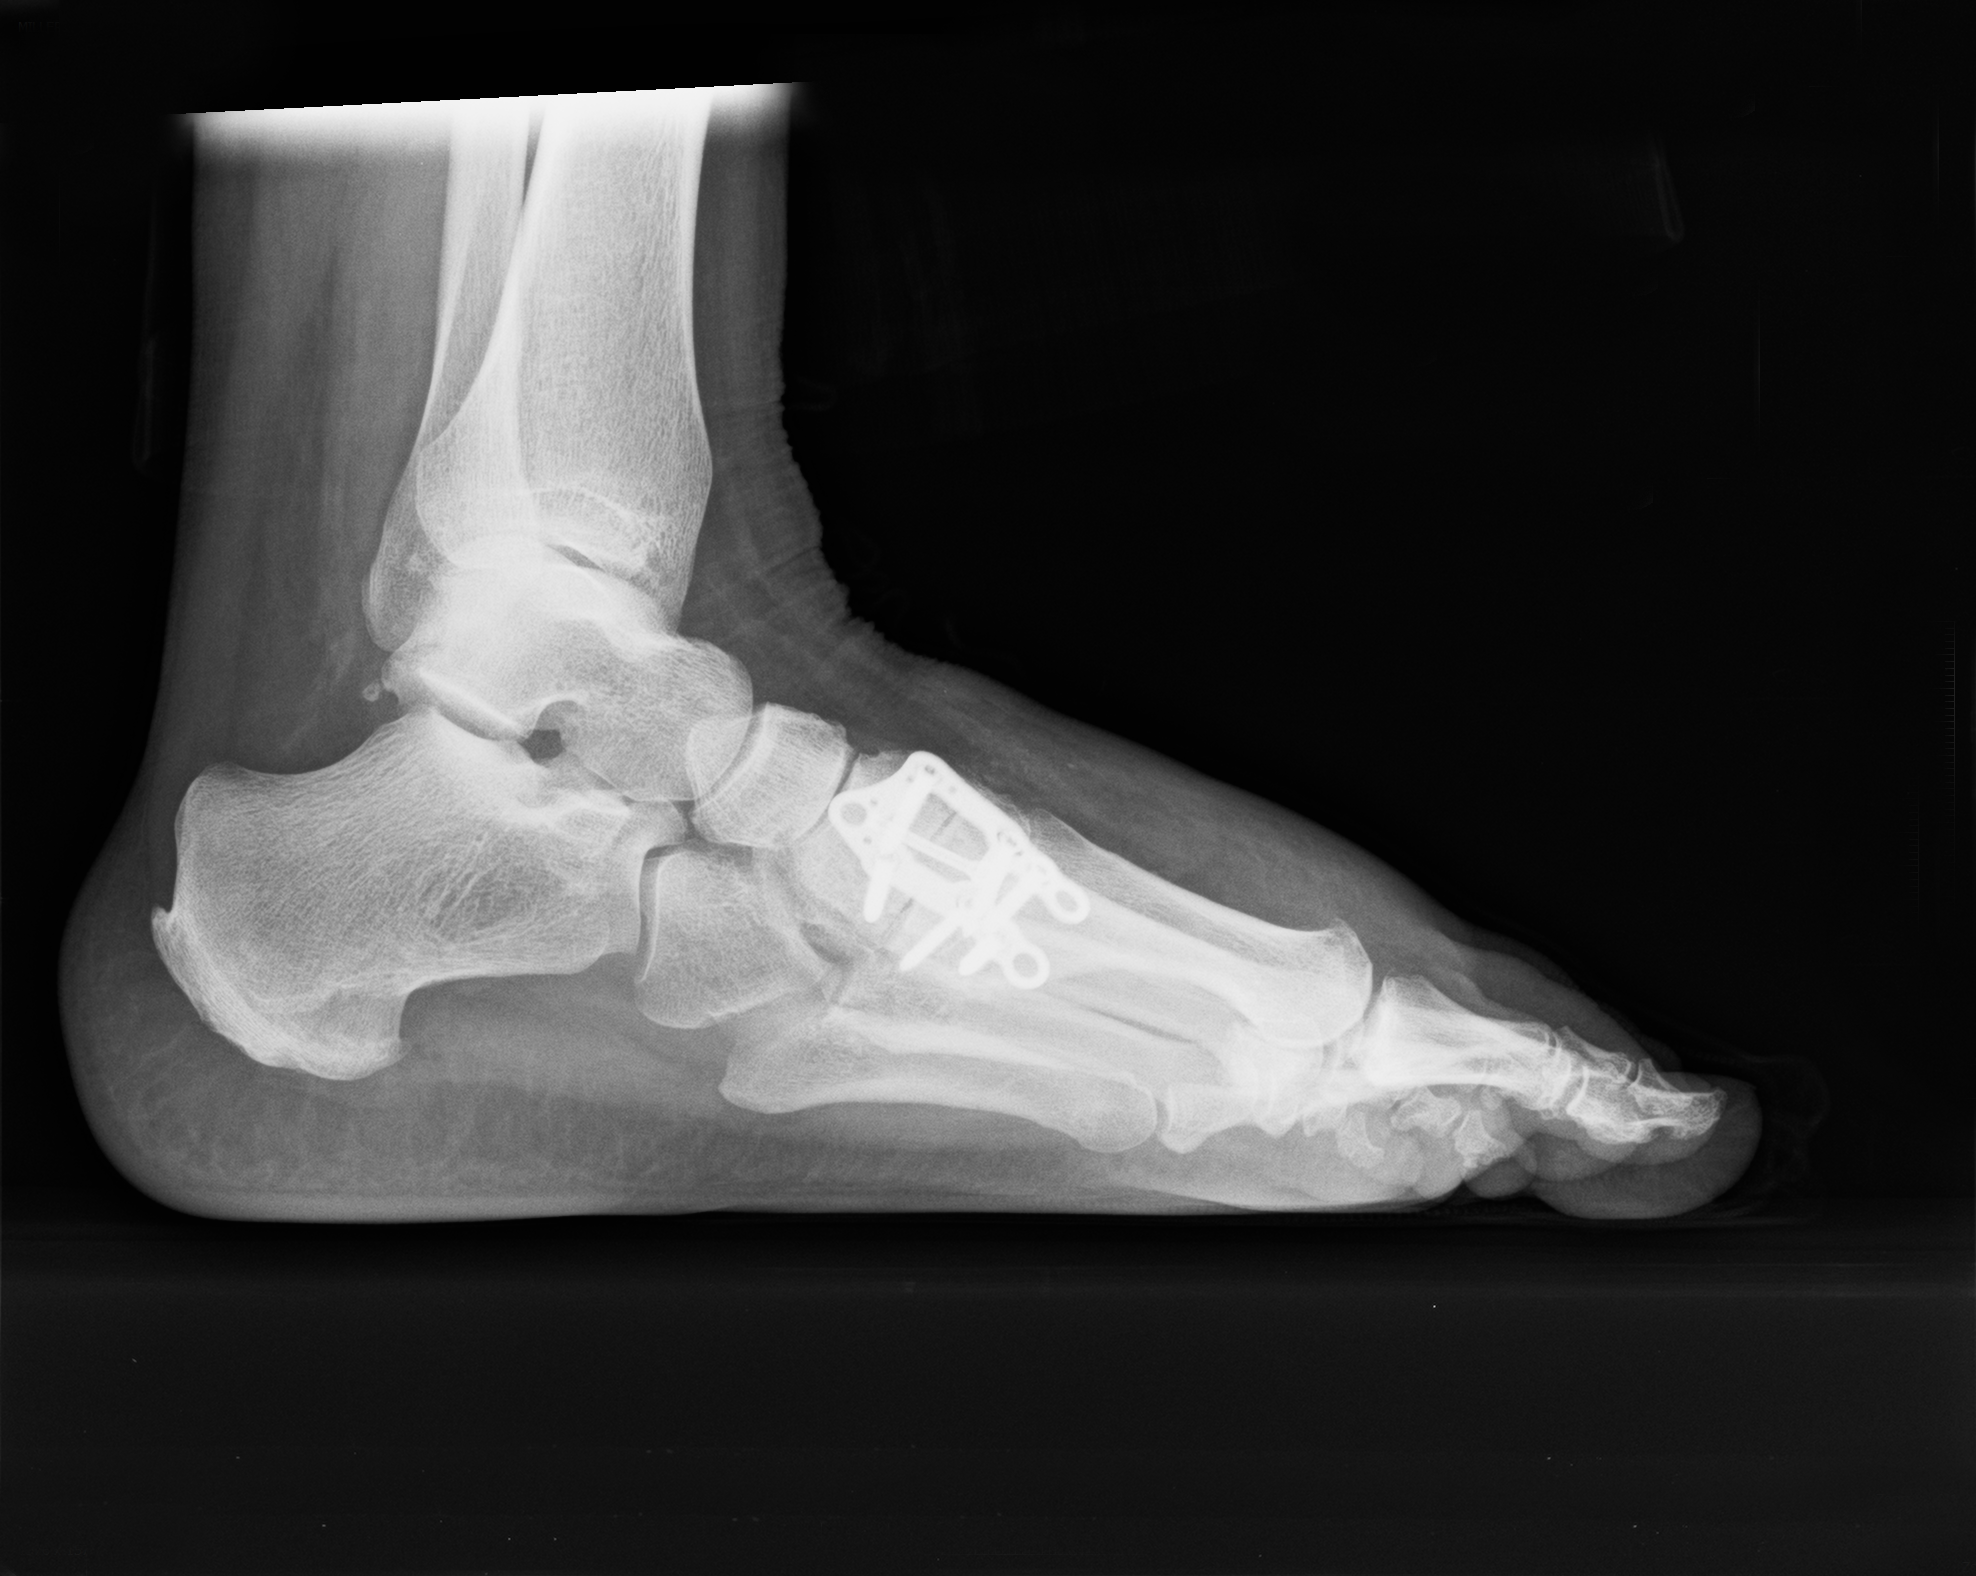

NCJ Fusion

Navicular-Cuneiform Joint Fusion

To reduce pain and deformity due to arthritis in the joint. Read more >>